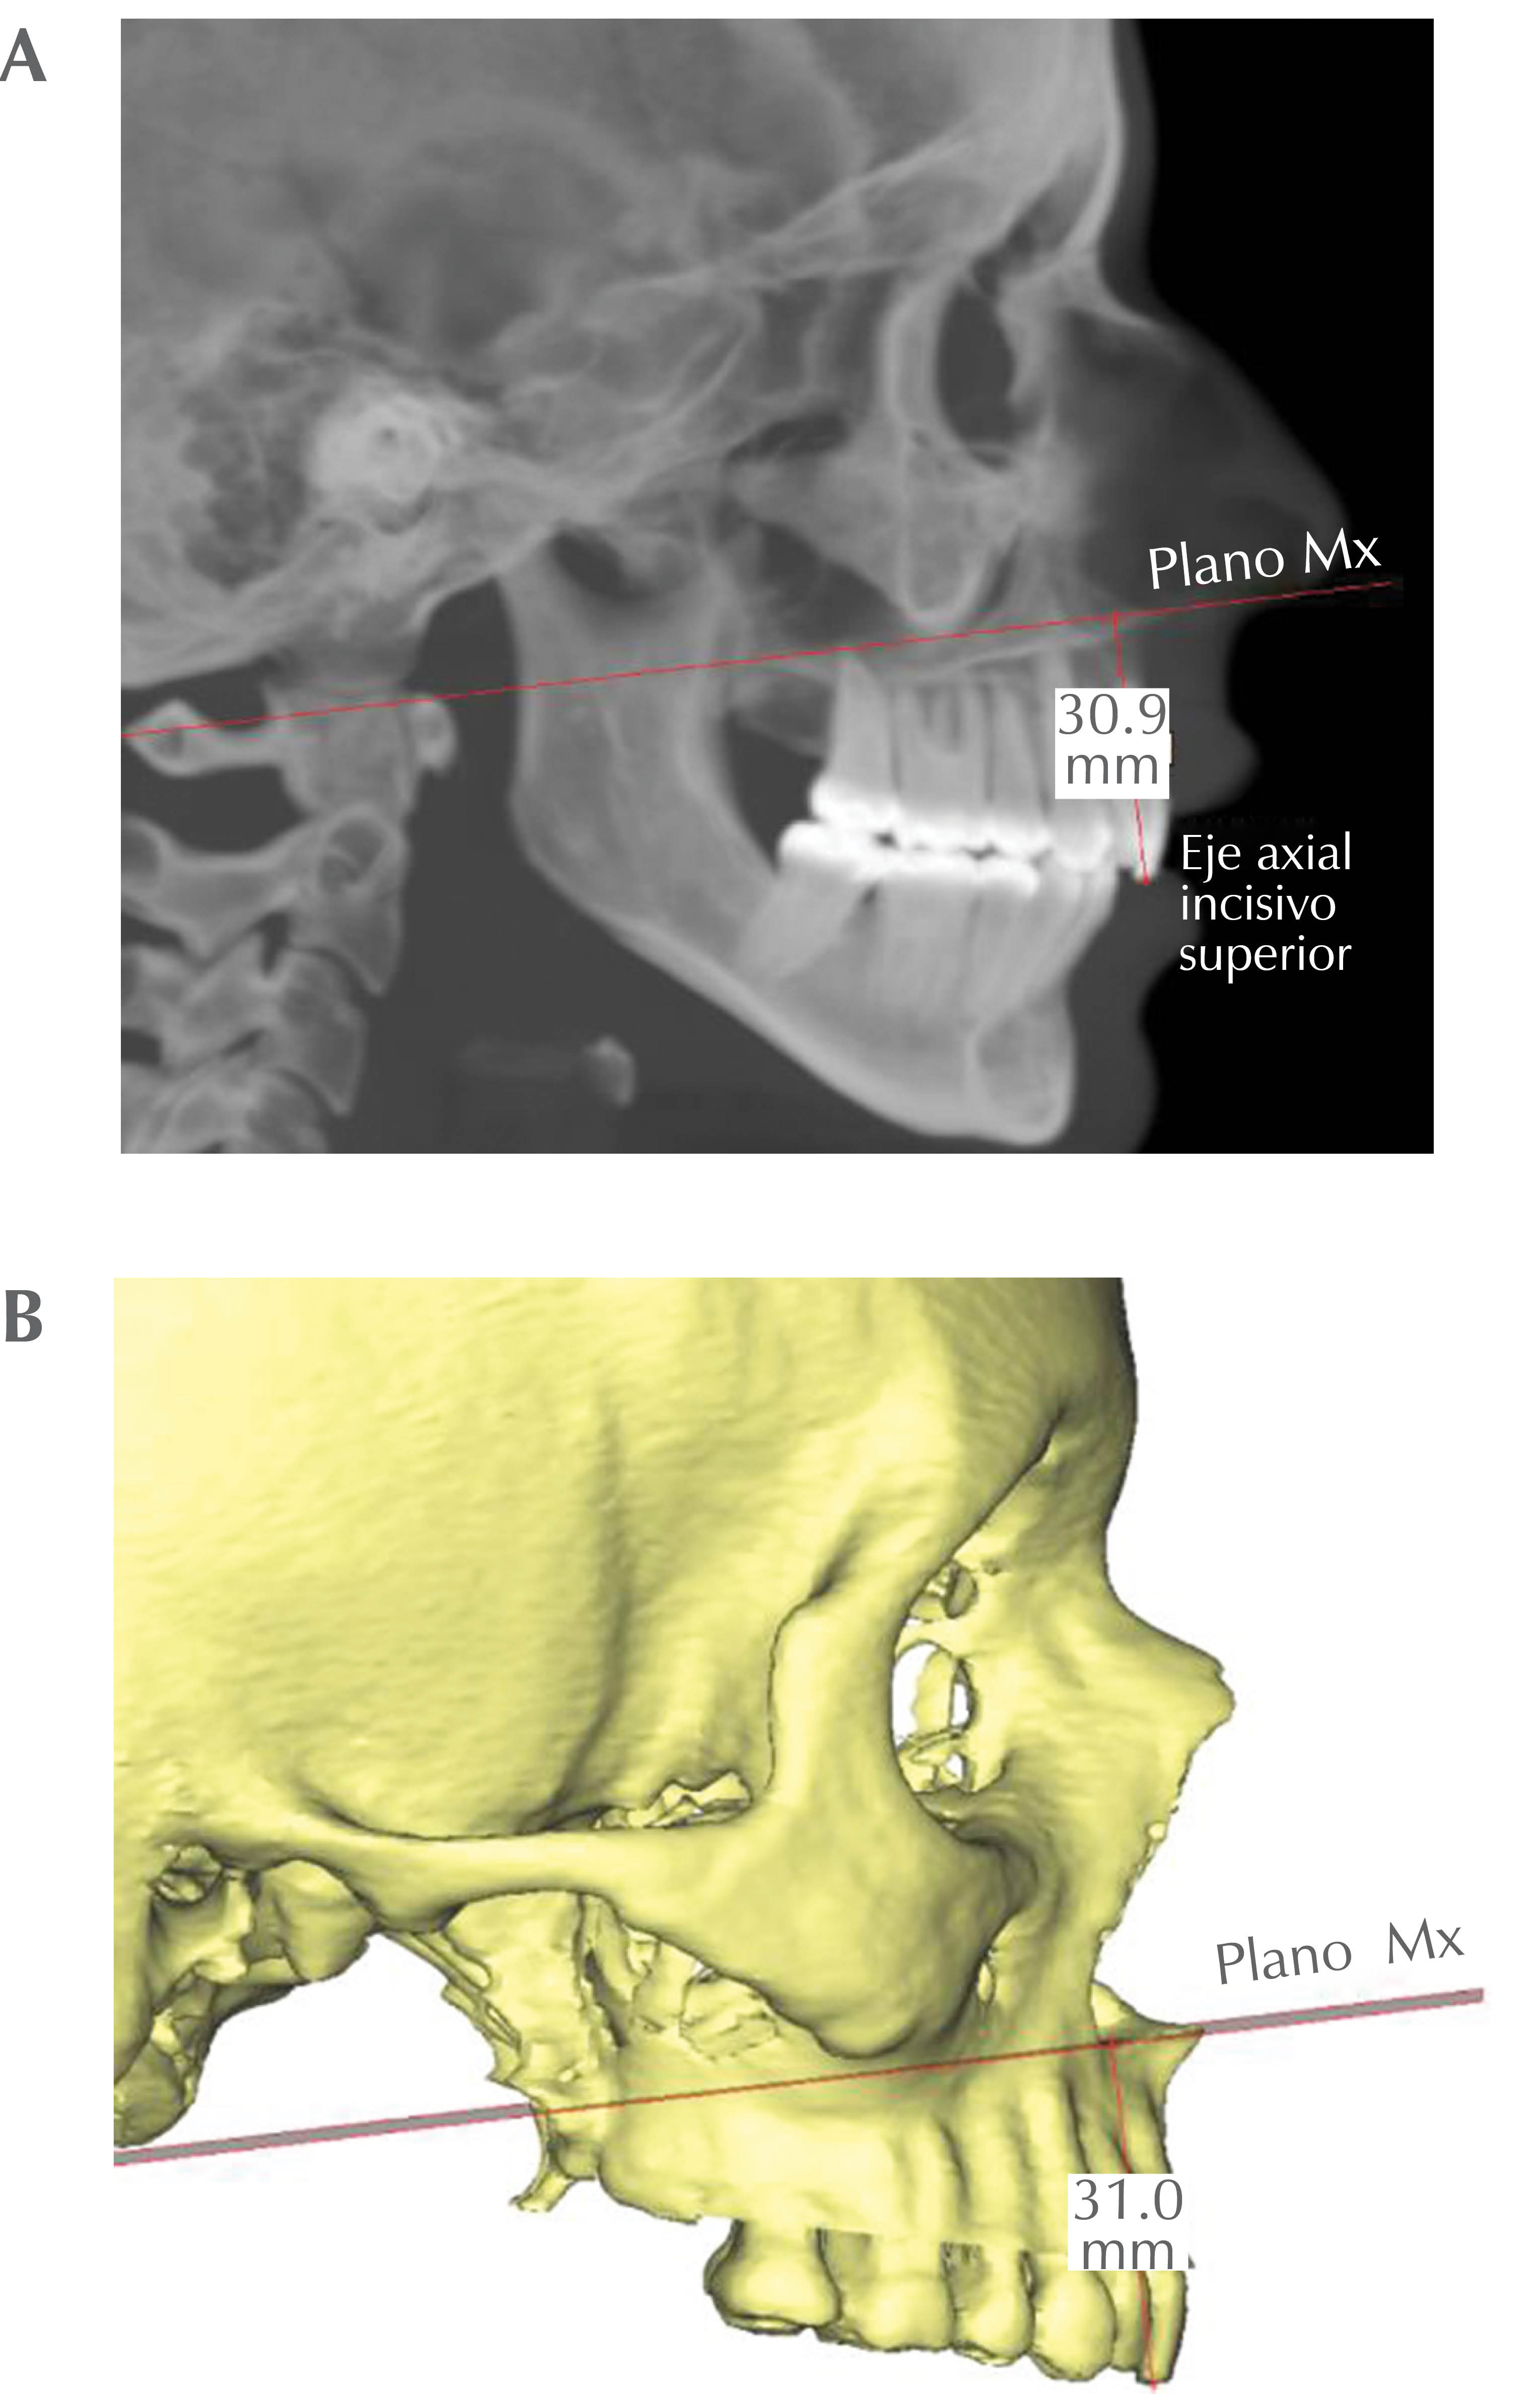

Para ejemplificar algunas de las cuestiones que debemos tener en cuenta para que nuestras mediciones sean correctas, hablaremos de las distancias entre dos puntos, entendiendo que una línea recta, por definición es el segmento de una sucesión de puntos en el espacio, entonces una medida cefalométrica entre un punto y una línea se convierte en la distancia entre un punto cefalométrico determinado y un punto de la sucesión de puntos que forman esa línea, en cefalometría 2D no tienen mayor relevancia este aspecto, pero el ejemplo de las Figuras 7A, 7B, 7C y 7D se observa cómo se deben hacer las mediciones. En este ejemplo medimos la distancia entre el punto Mx (maxilar: punto equidistante entre la espina nasal anterior y la espina nasal posterior) y la vertical pterigomaxilar (Mx-VPt) del autor Trujillo. En cefalometría 2D generamos una vertical que pase por el punto VPt (el punto más inferior de la fisura pterigomaxilar) y medimos la distancia entre el punto Mx y un punto de esta vertical en línea recta horizontal (Figuras 7A y 7B). En cefalometría 3D tenemos que contemplar el otro eje, ya que las mediciones no sólo pueden ser anteroposteriores o superoinferiores, sino que también mediolaterales. Esto nos estrega mayor precisión a la hora de recolectar datos de los estudios de imagen, pero debemos entender los principios para asegurar que los datos recolectados son los reales, en las Figuras 7C y 7D observamos cómo una distancia desde el punto Mx a un punto central en un plano vertical que pase a través del punto Pt derecho y Pt izquierdo.

• 6. 1-PMx: angulación del incisivo superior con respecto al plano maxilar; medición del ángulo formado por el eje axial del incisivo superior (1) con el plano maxilar (PMx) (Figura 13).

Figura 7A

Figura 7B

Figura 7C

Figura 7D